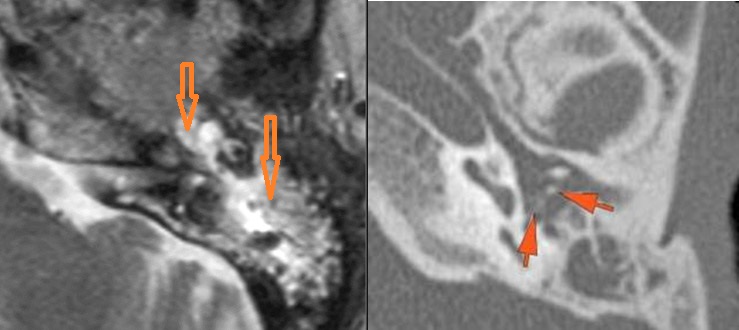

The mastoid septae are eroded. [Yes/No]

The sigmoid plate of the mastoid is eroded. [Yes/No]

There are dural reactive changes or a subperiosteal/epidural abscess along the sigmoid plate of the mastoid displacing the adjacent sigmoid sinus. [Yes/No]

The roof of the mastoid and middle ear are eroded. [Yes/No]

The inner ear, in particular the lateral semicircular canal and the cochlea are eroded or otherwise abnormal. [Yes/No]